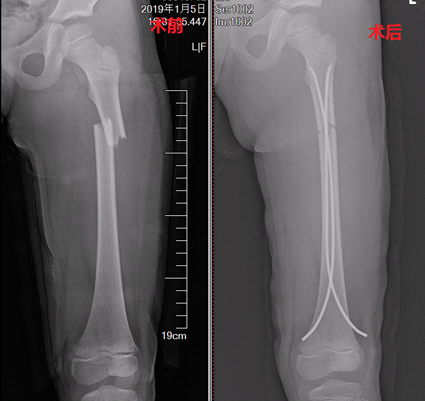

2019年1月8日,我院骨科首例弹性髓内针技术项目应用于一位5岁股骨骨折患儿,整个手术时间仅40分钟;术中出血少,仅10ml。即减少了患儿及家属长期牵引带来的痛苦,又避免了患者术后遗留长的手术疤痕。术后家长对我们的工作十分满意,而患儿的笑声更是对我们努力最大的认同。

术前术后对比照片